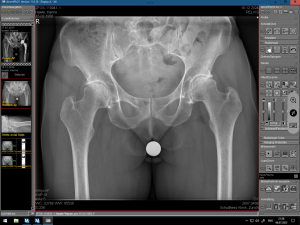

(Bilder: 1-3 Röntgenbild vor der OP mit Arthrose der linken Hüfte,